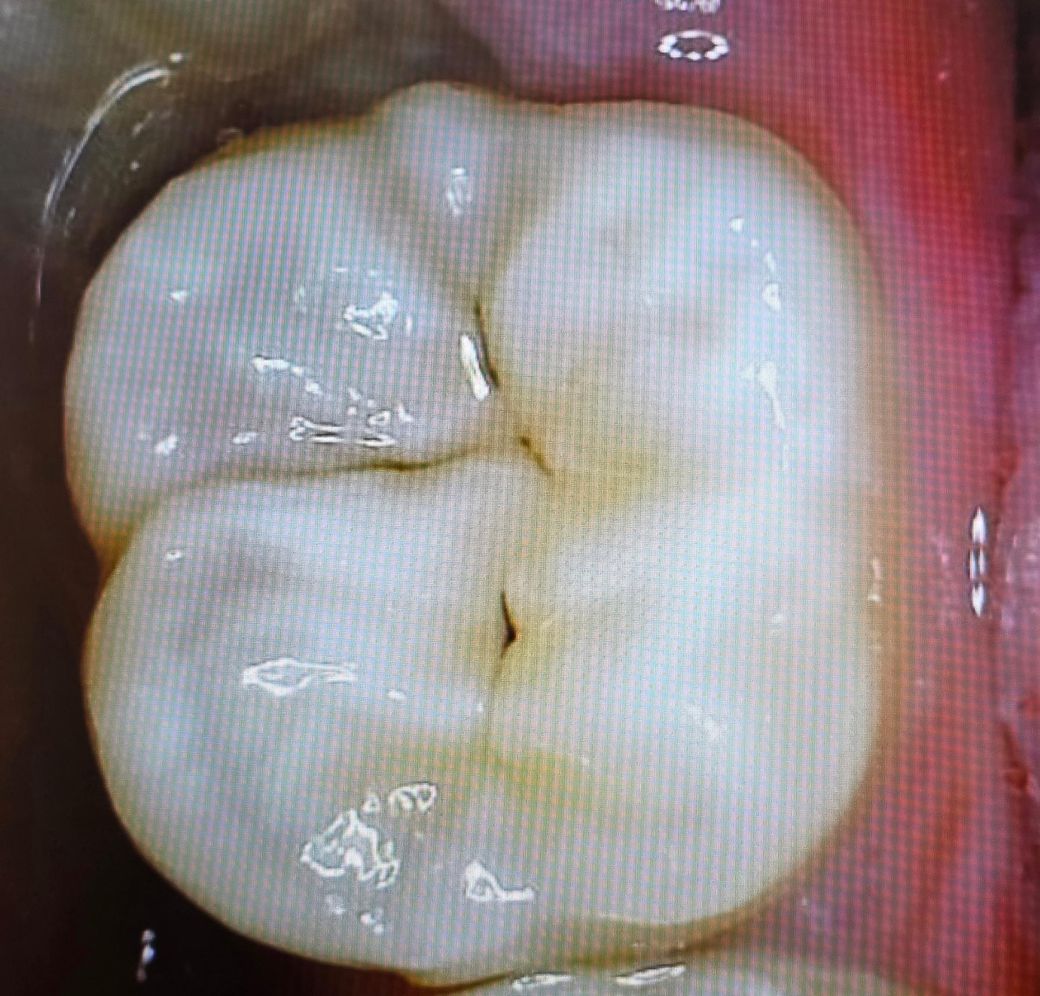

20살 아이 충치가 있다고 합니다

초기충치여서 조금 지켜봐도 되는지 아니면 치료가 필요한 충치 인가요?

둘다 충치의 양상이고, 엑스레이 찍어보면 좋을 것 같습니다. 치과를 한번 가보시기 바랍니다.